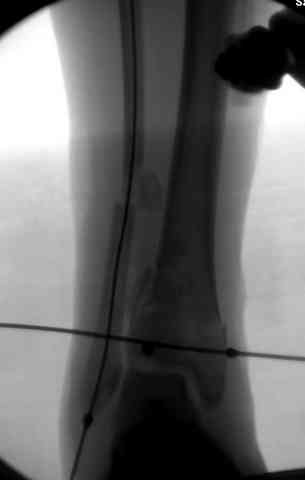

Здесь выставлена пара случаев перелома пилона, оба

случая леченные этапным наружным фиксатором.

Второй случай фиксирован аппаратом Илизарова.